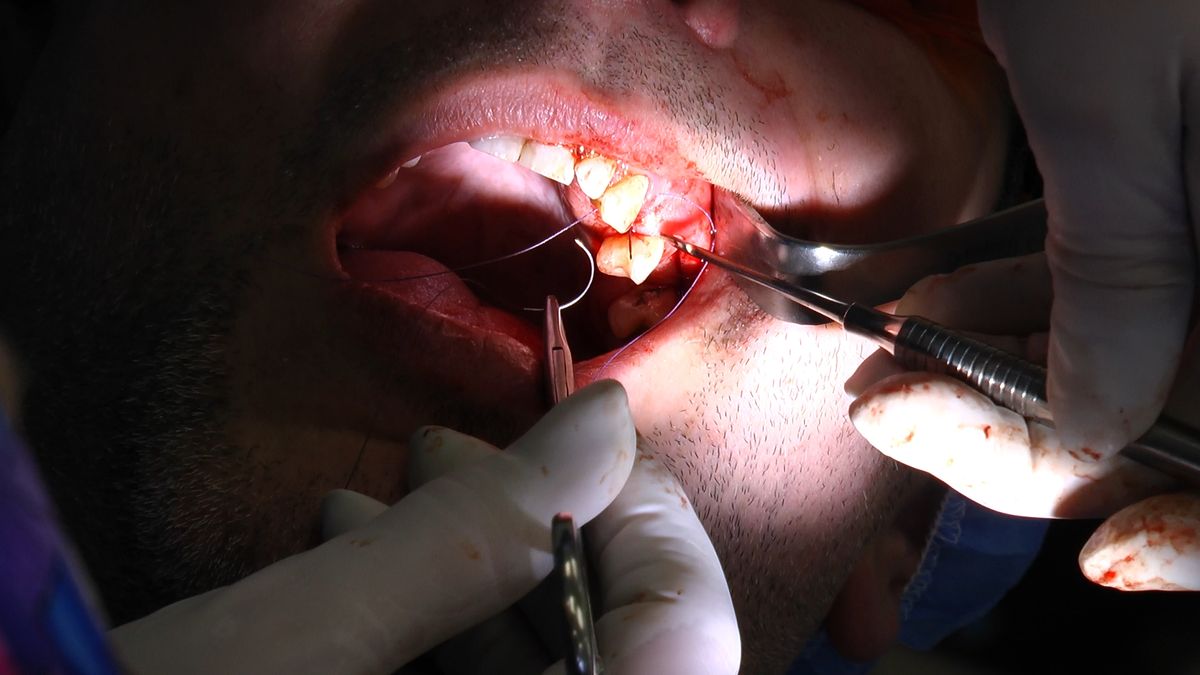

Pierwszy weekend 2019 roku w Instytucie Vivadental, to doskonałe otwarcie kolejnego roku edukacyjnego i szkolenia naszych Kursantów. W drodze do sukcesu w implantologii zdobywają wiedzę i umiejętności, a każdy kolejny zabieg to impuls i inspiracja do twórczego rozwoju w leczeniu własnych Pacjentów. Rozpoczęliśmy od sesji praktycznej implantologicznej właśnie z udziałem Pacjentów, na której dominowały samodzielne zabiegi wykonywane pod kierunkiem Mentorów – dr n.med. Violetty Szycik i dr n.med. Magdaleny Kisłowskiej – Syryczyńskiej. W ciągu dwóch dni zabiegowych przyjęliśmy 14 Pacjentów, przeprowadziliśmy zabiegi chirurgiczne, zabiegi regeneracyjne tkanki kostnej i augmentacji oraz wszczepiliśmy 20 implantów systemu Axiom. W ramach panelu edukacyjnego Sukces Twojego Biznesu odbyły się kolejne zajęcia z NLP, na których nasz Mentor Mariusz Wójcik z Gdańskiej Akademii Umiejętności Menedżerskich, kontynuował wprowadzenie do psychologii i podstaw kierujących decyzjami Pacjentów. Ćwiczenia w wesołej i koleżeńskiej atmosferze były niezwykle pouczające, a jednocześnie stanowiły idealną odskocznię po wyczerpujących zabiegach.